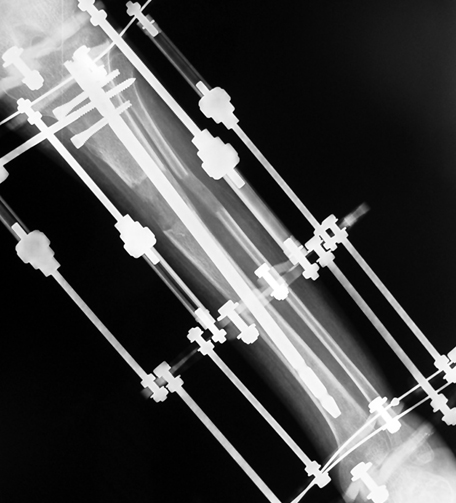

3. POSTTRAUMATIC LOWER LIMB SHORTNESS (MALUNION)

This type of shortness occurs after a fracture heals in a shortened position. Most cases are seen in adults and can be treated with one lengthening operation. Additional deformities can be corrected simultaneously. Most of these cases can be treated with lengthening over nail or just corrections and intramedullary nailing.